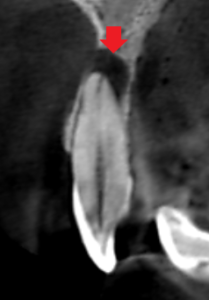

上顎側切歯の矢状断のCT画像です。

赤い矢印の先に膿の影が認められます。膿は唇側の歯槽骨を破り、

口蓋側の歯槽骨もペラぺラになる程の大きさでした。